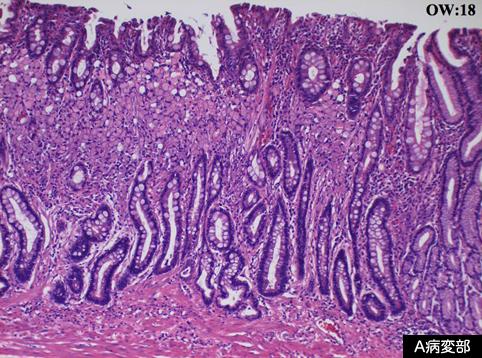

其他部位有胃腺瘤,对于癌灶行内窥镜下粘膜切除术(EMR)后,又对胃腺瘤实行补充切除的IIa+IIIb型早期胃癌

恶性上皮性肿瘤/印戒细胞癌

病理切片(微观)

0型(表在型)/IIa型(IIa+IIb)

35~40

m